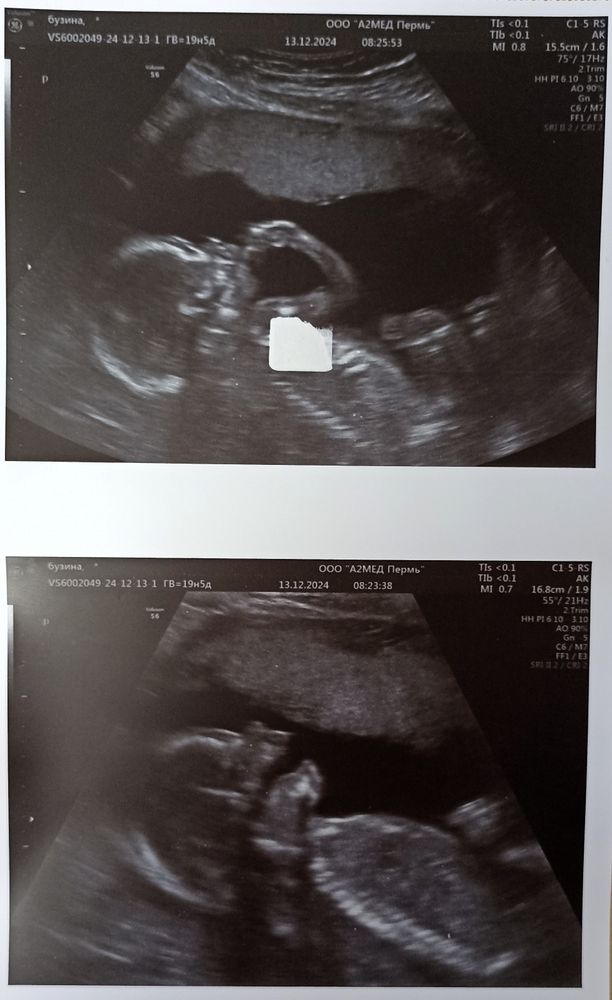

Пол малыша я не смотрела, отвернулась. Папаня все смотрел и даже снимал, но пол совсем не понял. Как и бабушки по видео не разобрали😀 Но на бумажке мы его получили, вечером узнаем всей семьей, но самое главное, у малыша все хорошо и мамино сердечко. Сообразительность наверное тоже мамина, все узи малышарик пытался пальчиком в ротик себе попасть, врач сказала, что скоро научится, а он раз и тут же попал, снимочек такого сладкого момента и зевочка на память💜